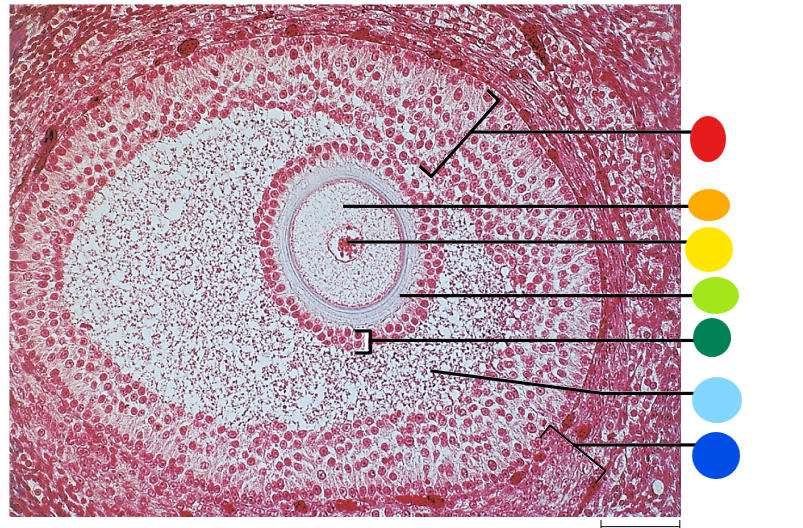

red

primary oocyte

orange

zona pellucida

yellow

granulosa cells

light green

developing thecal cells

What is this

secondary follicle